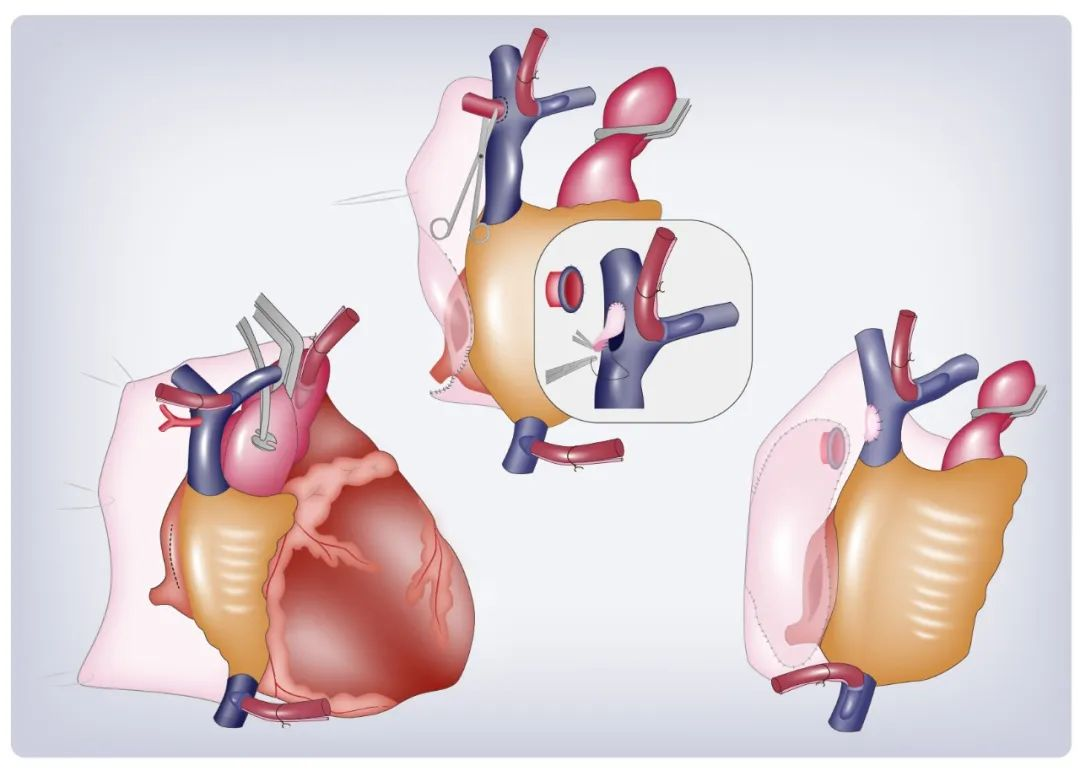

论文插图设计

滑动查看更多 点击查看大图